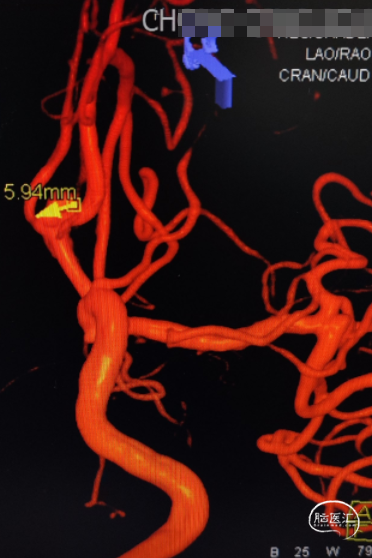

完善头颅CTA显示:前交通动脉瘤、左侧大脑中M1段末端动脉瘤。

DSA造影确认前交通动脉瘤、左侧大脑中M1段分叉部动脉瘤。

前交通动脉瘤5.94mm*4.12mm,瘤体呈分叶状。

患者右侧大脑前发育纤细;后循环血管无明显异常。